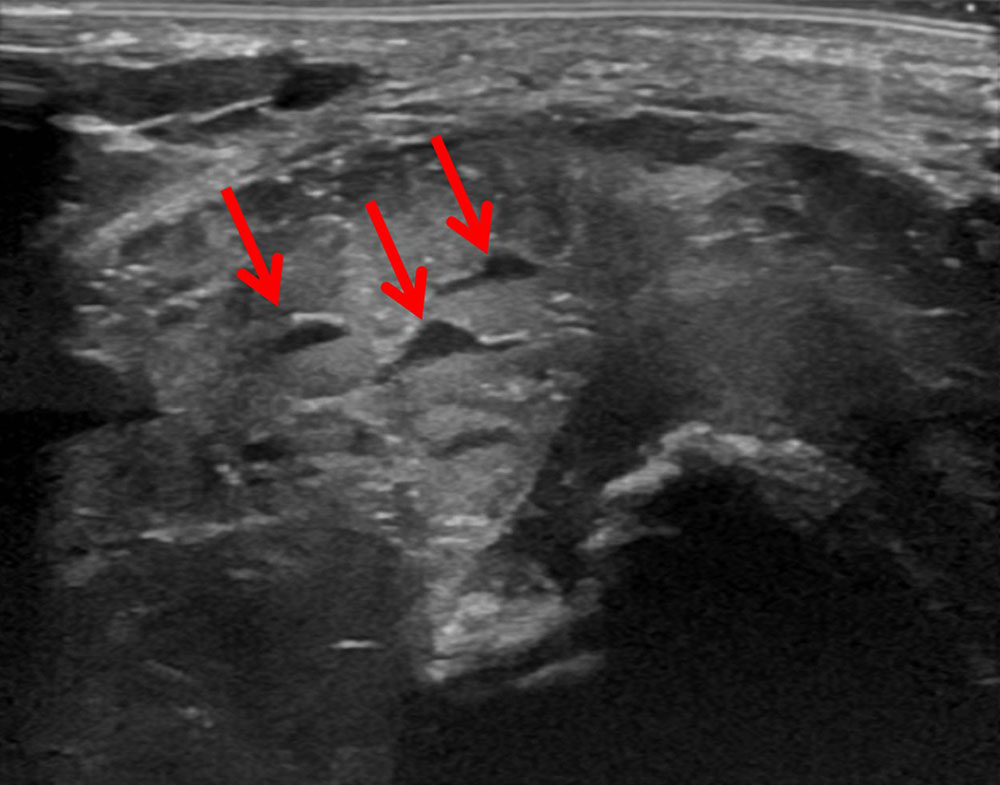

• Extensive thrombi within the venous malformation in imaging (especially visible in MRI and sonography) and large-volume intramuscular venous malformation